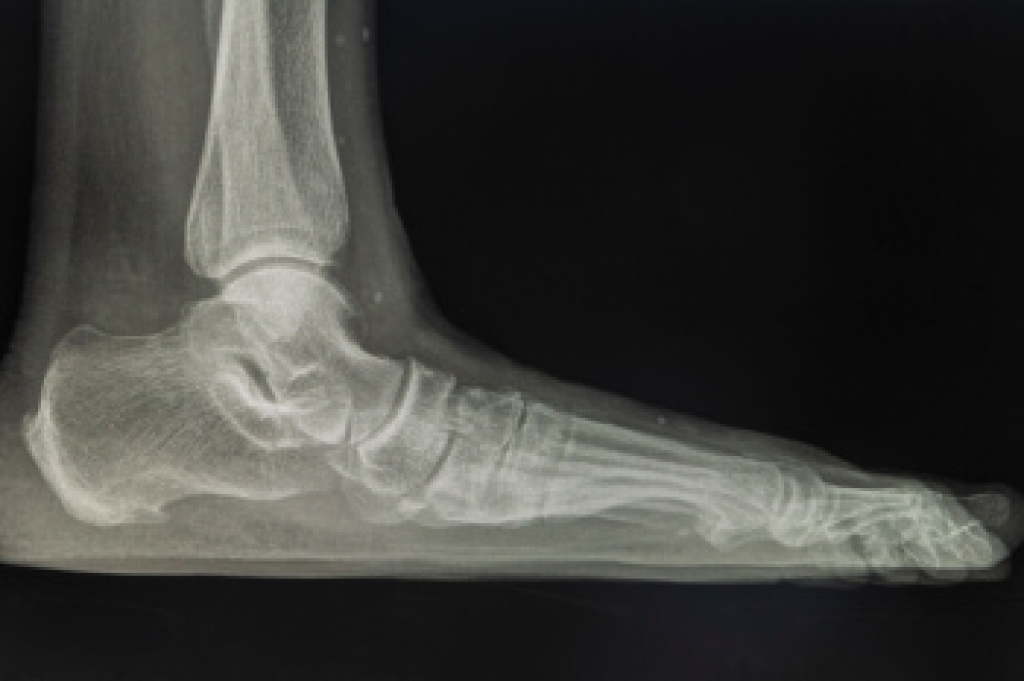

What Are Flat Feet?

Flatfoot is a condition in which the arch of the foot is depressed and the sole of the foot is almost completely in contact with the ground. About 20-30% of the population generally has flat feet because their arches never formed during growth.

- Flat look to one or both feet